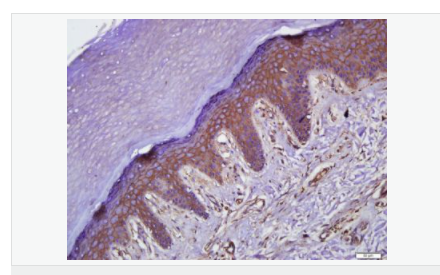

| 產(chǎn)品應(yīng)用 | WB=1:500-2000 ELISA=1:5000-10000 IHC-P=1:100-500 IHC-F=1:100-500 Flow-Cyt=1μg/Test ICC=1:100 IF=1:100-500 (石蠟切片需做抗原修復(fù)) not yet tested in other applications. optimal dilutions/concentrations should be determined by the end user. |

| 產(chǎn)品介紹 | This gene encodes an integral membrane protein which is located at tight junctions. This protein may be involved in the formation and maintenance of the tight junction. The possibility of several alternatively spliced products has been suggested but the full nature of these products has not been described. [provided by RefSeq]. Function: May play a role in the formation and regulation of the tight junction (TJ) paracellular permeability barrier. Subunit: Interacts with TJP1/ZO1 and with VAPA. Subcellular Location: Membrane; Multi-pass membrane protein. Cell junction, tight junction. Tissue Specificity: Localized at tight junctions of both epithelial and endothelial cells. Highly expressed in kidney. Not detected in testis. Post-translational modifications: Phosphorylated upon DNA damage, probably by ATM or ATR. Dephosphorylated by PTPRJ. May be phosphorylated by PKC during translocation to cell-cell contacts. Similarity: Belongs to the ELL/occludin family. Contains 1 MARVEL domain. SWISS: Q16625 Gene ID: 100506658 Database links: Entrez Gene: 18260 Mouse Entrez Gene: 100506658 Human Omim: 602876 Human SwissProt: Q16625 Human SwissProt: Q61146 Mouse Unigene: 592605 Human Unigene: 4807 Mouse Unigene: 31429 Rat Important Note: This product as supplied is intended for research use only, not for use in human, therapeutic or diagnostic applications. |